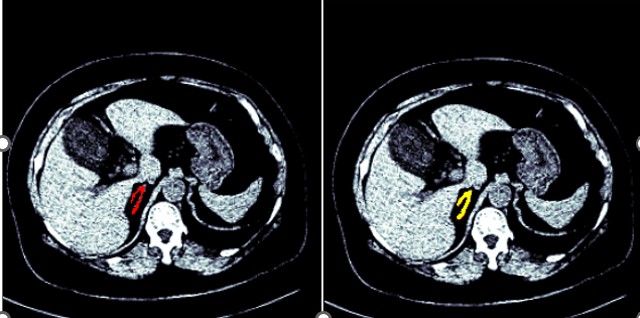

Figures 1 and 2 show the segmented model output for both right and left adrenal gland from a CT scan image from the AMOS dataset.

Figure 2: Segmentation of a left adrenal gland (AMOS dataset)